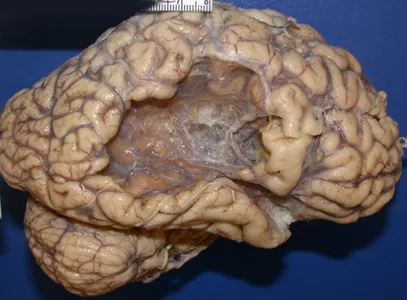

Mózg z lożą, która powstała na skutek przebytego zawału (udaru) mózgu.

Ryc. C – obraz makroskopowy starego zawału mózgu (Kumar V., et al., 2014).

Popatrzcie na obrazek z ogniskiem udaru niedokrwiennego – Ryc. C. Osoby, które wnikliwie przeczytały poprzedni akapit mogą chcieć zobaczyć na zdjęciu obszar martwicy skrzepowej. Wynika to wprost ze zdania, że martwica skrzepowa dotyczy obszaru niedokrwienia. Nic bardziej mylnego. Na zdjęciu prezentuje się jama poudarowa, która przyżyciowo wypełniona jest płynem mózgowo-rdzeniowym. W jednym z akapitów napisałem, że tkanka nerwowa jest wyjątkowa pod względem funkcji jak i sposobu dokonywana się martwicy. Pierwszym etapem po niedokrwieniu są wydarzenia na poziomie molekularnym. Obejmują one spadek fosforylacji oksydacyjnej i zaburzenia jonowe neuronów, co prowadzi do obrzęku cytotoksycznego (Frizzell J. P., et al., 2005)3. Na poziomie mikroskopowym dochodzi do pojawienia się wykładników martwicy skrzepowej! Jednak otaczające ognisko astrocyty i mikroglej bardzo szybko zostają zmobilizowane do uprzątania martwiczych komórek. Dokonują tego na zasadzie trawienia. Lizat komórkowy ma konsystencje płynną stąd określenie martwica rozpływna. Całkowite posprzątanie ogniska udarowego przez mikroglej pozostawia różnej wielkości, ziejącą jamę – pustą przestrzeń, w której kiedyś mogły być zlokalizowane czyjeś wspomnienia, umiejętności czy podstawowe funkcje życiowe.

Zdjęcie przedstawia obszerną jamę poudarowej prawej półkuli mózgu.

Ryc. D – obszerna jama poudarowa prawej półkuli mózgu obejmująca swoim zasięgiem płat czołowy, skronoiowy i ciemieniowy. Taki obraz może powstać przy obturacji tętnicy środkowej mózgu.